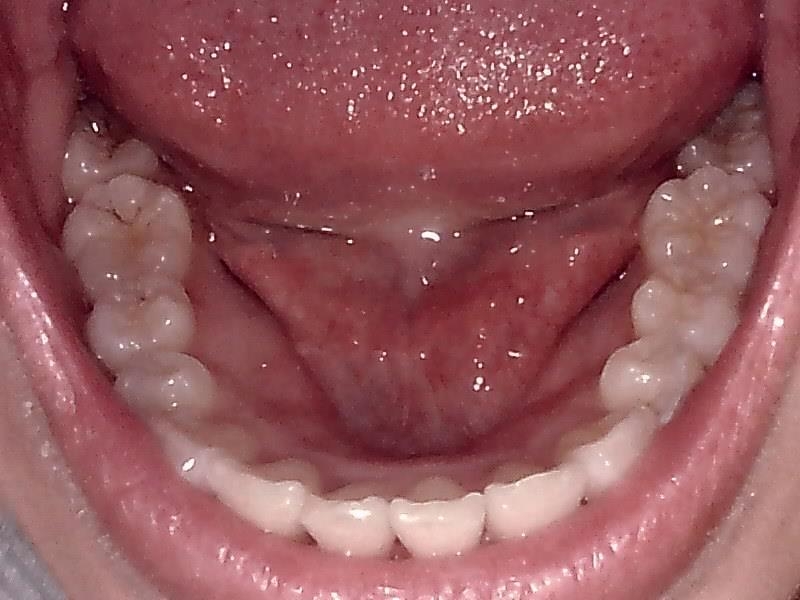

下顎